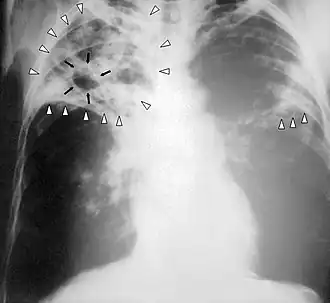

Radiografía de tórax

Rx de tórax de un caso de tuberculosis.

La radiografía es esencial en el diagnóstico de la enfermedad. Las lesiones típicas radiológicas son apicales, en hemitórax derecho, en segmentos posteriores y en general forman cavidades.

La herramienta para el diagnóstico de caso de tuberculosis es la bacteriología (baciloscopía y cultivo) por su alta especificidad, sensibilidad y valor predictivo. En aquellas situaciones donde los estudios bacteriológicos no sean concluyentes será necesario realizar el seguimiento diagnóstico de acuerdo con la organización de la red de servicios de salud, utilizando otros criterios: clínico, epidemiológico, diagnóstico por imágenes, inmunológico, anatomopatológico.